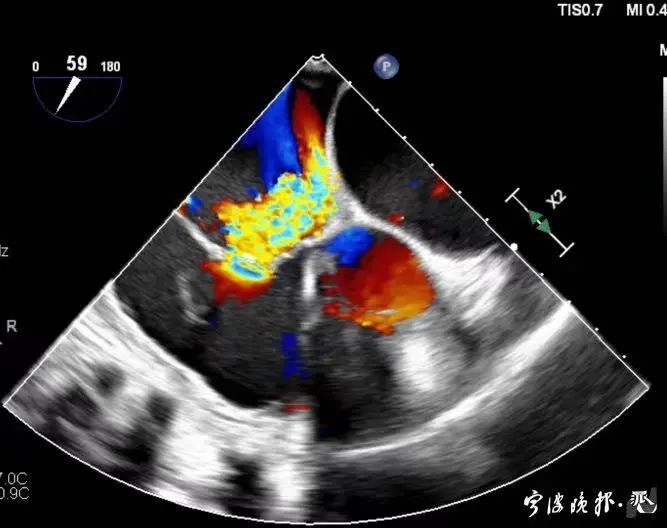

術(shù)后食道心超示三尖瓣反流消失

得知可以微創(chuàng)手術(shù),陳大爺一家決定放手一搏。寧波市醫(yī)療中心李惠利醫(yī)院心臟瓣膜中心團(tuán)隊(duì)反復(fù)就術(shù)前準(zhǔn)備、手術(shù)步驟及術(shù)后可能出現(xiàn)的各種情況做了預(yù)案。3月4日,陳大爺?shù)氖中g(shù)成功進(jìn)行,術(shù)中得到LuX-Valve經(jīng)導(dǎo)管三尖瓣置換術(shù)原創(chuàng)團(tuán)隊(duì),上海長(zhǎng)海醫(yī)院陸方林主任團(tuán)隊(duì)的鼎力支持,術(shù)后陳大爺?shù)男呐K三尖瓣反流立即消失。術(shù)后瓣膜中心CCU(心臟監(jiān)護(hù))團(tuán)隊(duì)和心內(nèi)科團(tuán)隊(duì)迎接一個(gè)又一個(gè)右心瓣膜置換后的血流動(dòng)力學(xué)改變等帶來的挑戰(zhàn),克服種種難關(guān),二周后患者進(jìn)入早期心臟康復(fù)。目前陳大爺已經(jīng)順利出院,沒有胸悶氣急,生活自理,精神狀態(tài)也很好,瓣膜中心團(tuán)隊(duì)也在對(duì)他持續(xù)隨訪中。